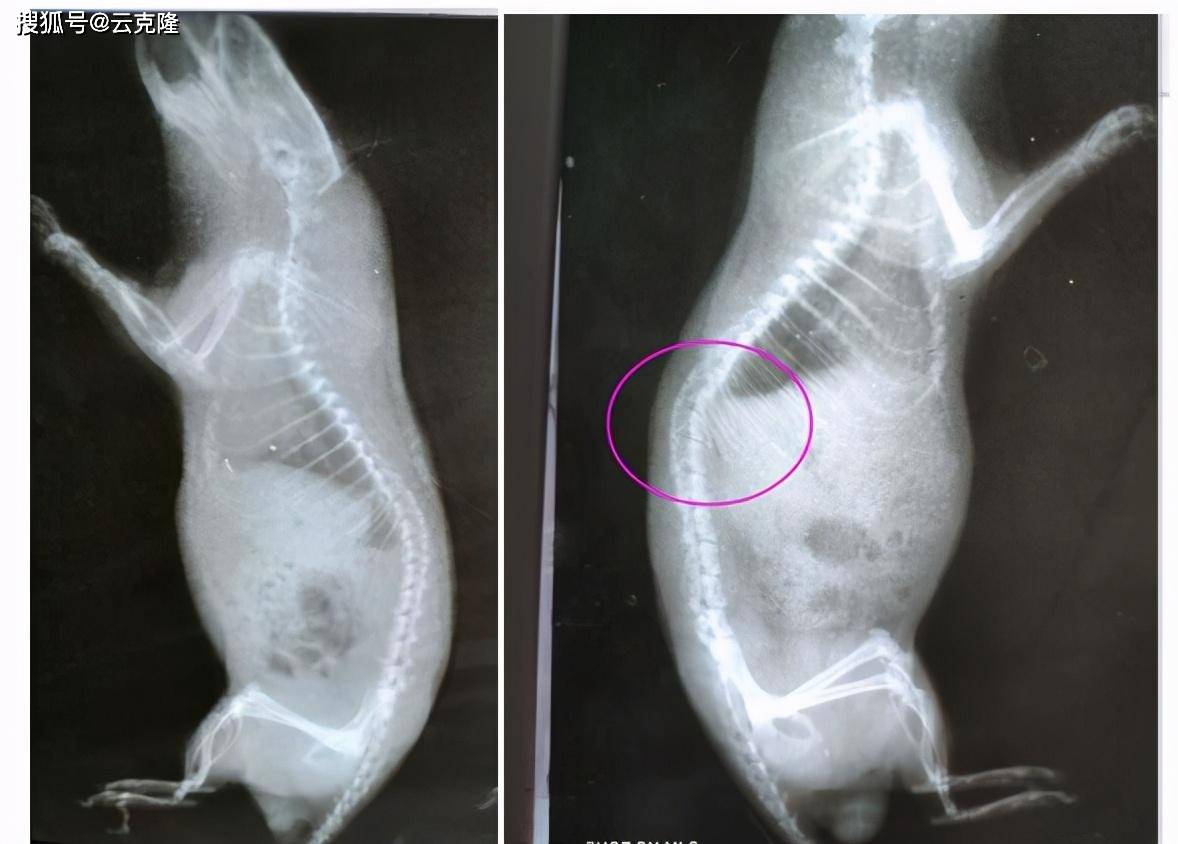

我做的脊髓横断模型 老鼠术后很难进食 一周后杀死尸解发现如图 请教